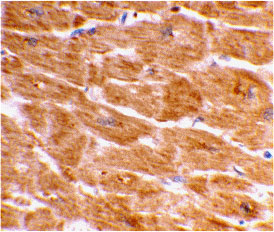

Immunohistochemical staining of human heart tissue using Caspase-1 antibody at 2 μg/mL. |